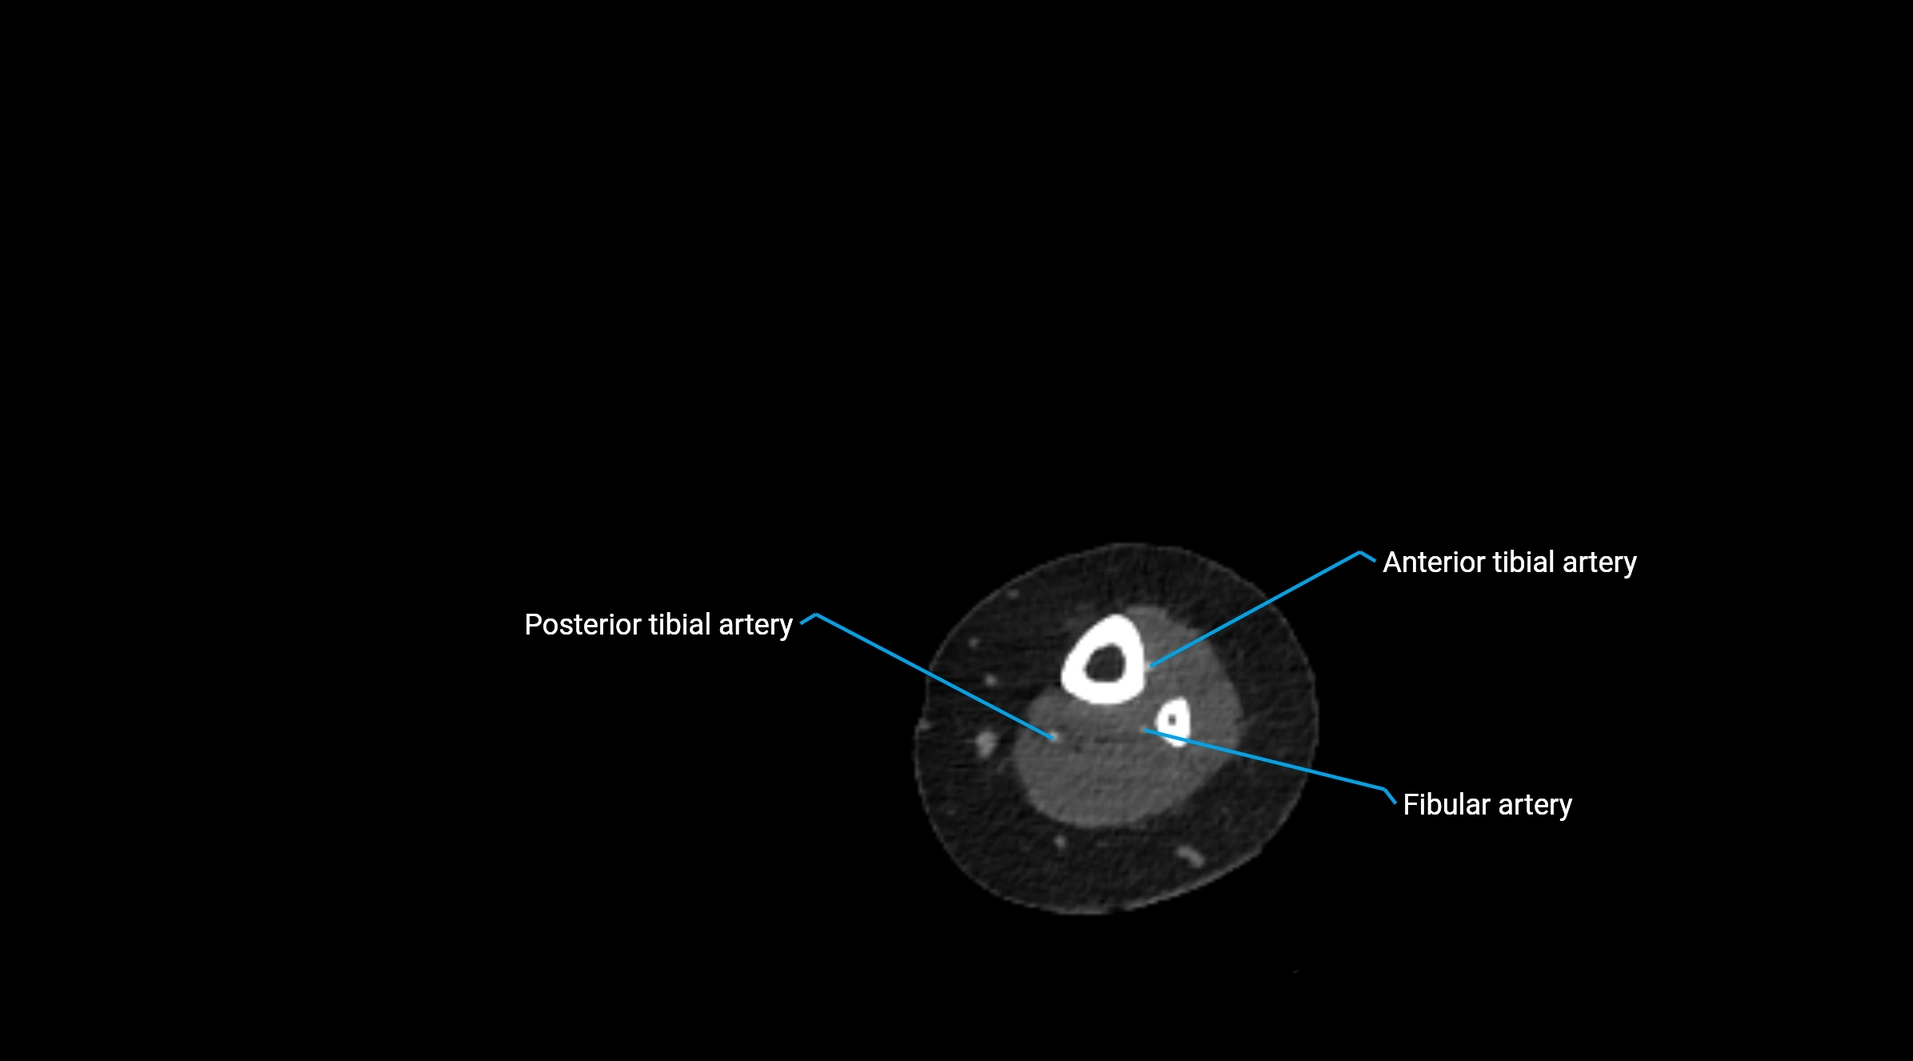

Contrast-enhanced CT (CTA):

• Gold standard for abdominal aortic imaging

• Provides excellent detail of lumen, wall, aneurysm, thrombus, and branch vessels

• Multiplanar and 3D reconstructions help in aneurysm measurement, stent graft planning, and dissection evaluation